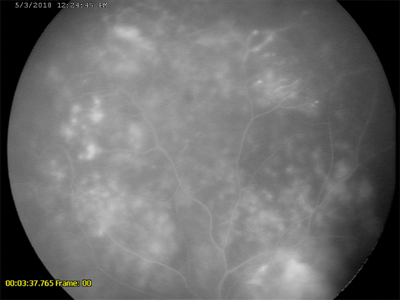

Figure 2a: RetCam image of fundus of child with Coat’s disease following laser treatment.

Figure 2b: Flourescein angiography of same patient, taken under general anaesthetic with RetCam.

Advances in digital fundal imaging in children have transformed diagnosis and monitoring of a wide range of children’s eye diseases. RetCam and newer more portable digital fundal imaging devices (such as PanoCam) are now routinely used in infants and young children for the documentation of retinal disease (Figure 2). Digital imaging is particularly important for the diagnosis, monitoring and documentation of retinopathy of prematurity (ROP) [2]. It has significantly enabled trained non-medical users to send images obtained in the neonatal intensive care unit (NICU) to a remote expert for interpretation - true ‘telemedicine’. This principle may be transformative for the delivery of high quality ROP care in the developing world where paediatric ophthalmologists are scarce. Digital documentation of retinal haemorrhages in cases of suspected non-accidental injury is important both clinically and from a medico-legal aspect (Figure 3).

Anti-VEGF intravitreal injections have also been utilised in other areas of paediatric ophthalmology, such as in Coat’s disease, Best’s disease and in the treatment of subretinal neovascular membranes in inflammatory eye disease.